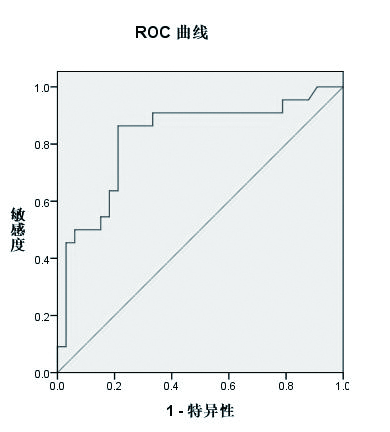

采用SPSS19.0进行统计学分析,计量资料0以均数±标准差(x±s)表示,采用独立样本t检验,计数资料采用χ2检验。对IJV/CCA截面积比值和PLR试验引起的ΔCO值进行相关分析,采用Pearson分布方法。采用受试者工作特征(ROC)曲线评价超声下IJV/CCA截面积比值和PLR试验引起的ΔCO值预测容量反应性的准确性和阈值。计算曲线下面积[95%可信区间(CI)]、阈值、灵敏度及特异度,以P < 0.05为差异有统计学意义。本次样本量确定使用PASS软件计算,检验效能为90%(1~0.1)。

2.4 IJV/CCA截面积比值容量反应阳性组IJV/CCA截面积比值(1.38±0.55)明显小于容量反应阴性组截面积比值(2.16±0.68),差异有统计学意义(t=-4.66,P < 0.001)。IJV/CCA截面积比值为(1.68±0.71)mm,IJV/CCA截面积比值与PLR试验引起的ΔCO值有显著相关性(r=-0.67,n=55,P < 0.01)(图 5)。应用ROC曲线评价IJV/CCA截面积比值与PLR试验引起的ΔCO值, 其曲线下面积为0.823(95% CI: 0.703~0.943),相应阈值为1.65(灵敏度86.4%,特异度78.8%)(图 6)。

| 图 6 IJV/CCA截面积比值与ΔCO值的ROC曲线 Figure 6 The ROC curve of IJV/CCA cross-sectional area ratio and ΔCO value |

|

本研究发现IJV/CCA截面积比值与PLR试验引起的ΔCO值评估容量反应性有相关性,其灵敏度86.4%,特异度78.8%。同时,IJV直径、截面积与ΔCO值也存在较弱的相关性。说明IJV/CCA截面积比值评估容量反应性比IJV直径、截面积更可靠;此外,本研究发现CCA直径与截面积不适合评估容量状态。

IJV/CCA截面积比值最早用于小儿烧伤患者研究,该比值与CVP具有较强的相关性[16]。随后的一项研究表明,IJV/CCA截面积比值与CVP存在显著的相关性,敏感度90%,特异度83.36%[8]。研究还指出吸气末与呼气末IJV/CCA截面积比值分别为1.89±0.83和1.90±0.83,差异无统计学意义。这说明该比值不受呼吸影响。根据先前研究,该比值用于评估容量状态主要基于和CVP的比较,但CVP评估容量状态的准确性不高。本研究以PLR试验引起的ΔCO值为参考标准,结果显示IJV/CCA截面积比值小于1.65时具有较高的敏感度和特异度,可信度更高。